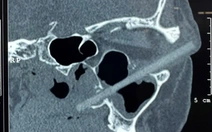

Trong phút nóng giận, ông Hùng mở cốp xe lấy hai con dao quay lại bàn nhậu và bất ngờ kề dao vào cổ rồi đâm vào ngực phải ông L. khiến nạn nhân bị thương tích 13%.